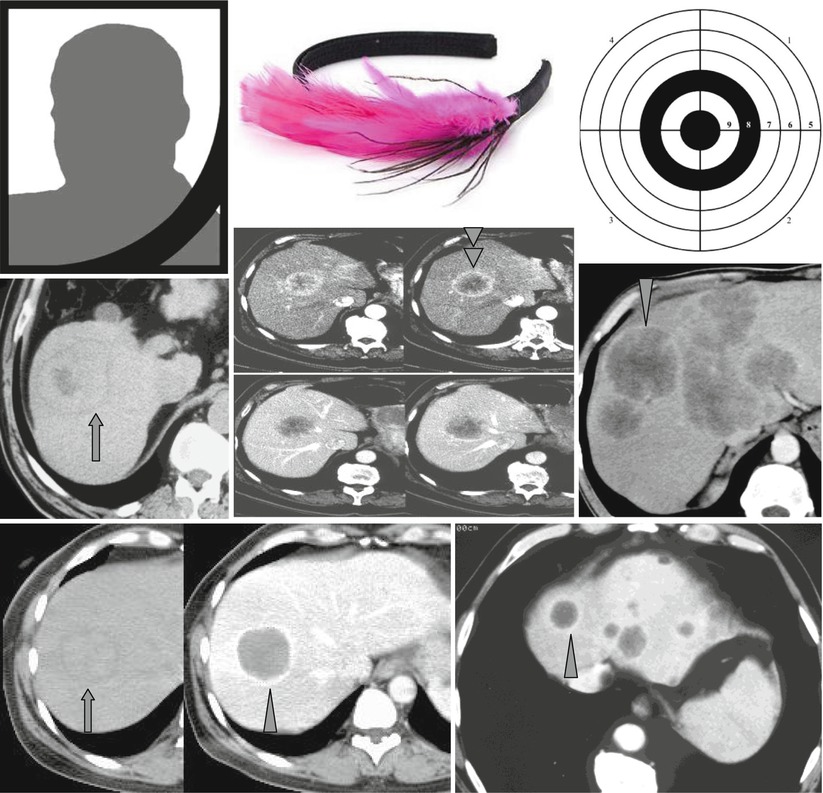

Picture frame vertebral body is a radiologic appearance in which the cortex of the vertebral body is thickened.

A descriptor for vertebral involvement by pagets disease of bonean isolated vertebral body is enlarged centrally osteoporotic and surrounded by a rim of osteosclerotic cortex which involves the anterior and posterior margins and vertebral end plates.

Paget disease of the l4 vertebra.

It is a result of disorganized new cortical bone formation after excessive osteoclastic activity causes the resorption of normal bone.

Funeral Frame Sign Rim Enhancement And Target Like Appearance

Sandwich vertebral body is a radiologic appearance in which the endplates are densely sclerotic giving the appearance of a sandwichthis term and pattern are distinctive for benign adult autosomal dominant osteopetrosis.

Despite increased radiologic density bone is fracture prone.

Sandwich vertebrae appears denser and more sharply defined.

This sign can be seen in patients with p aget disease.